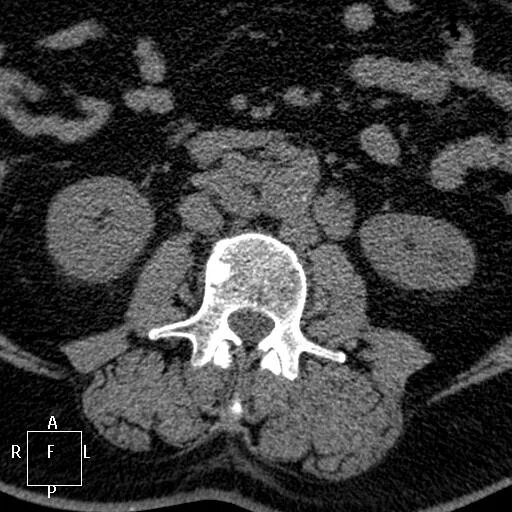

Метастазы в простате